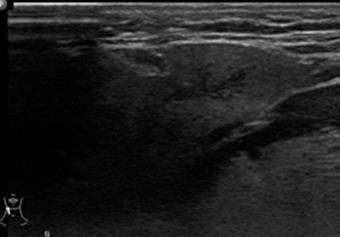

Ultrahangvizsgálat

Az ultrahang diagnosztikus használata az ultrahanghullám a vizsgálandó területen való áthaladásának és a különböző denzitású szövetek határfelületéről történő visszaverődésének kimutatásán alapszik (12.3. ábra). Az egyéb radiológiai eljárásokkal szemben számos előnye van: olcsó, széles körben hozzáférhető, könnyen kivitelezhető, fájdalmatlan, nem invasiv eljárás. Fő alkalmazási területe a nagy nyálmirigyek cysticus (folyadék tartalmú) elváltozásainak a tömör daganatoktól való elkülönítése. (A parotis mélyebben fekvő lebenye esetében a mandibuláról visszaverődő visszhangok félrevezetőek lehetnek.) A tumorok szövettani típusára azonban az információ nem specifikus, aspiratiós citológia vagy biopsia szükséges a kiegészítésre. Gyulladásos és obstruktív kórképek esetében a szialográfia több információt nyújt. A nyálkövek diagnosztikájában is hasznosan alkalmazható eljárás, bár a natív röntgenfelvétel és a szialográfia pontosabb adatokat nyújt a nyálkövek lokalizációjáról.

12.3. ábra. Ép submandibularis nyálmirigy ultra hangképe

(Dr. Dobai Ágnes anyagából)